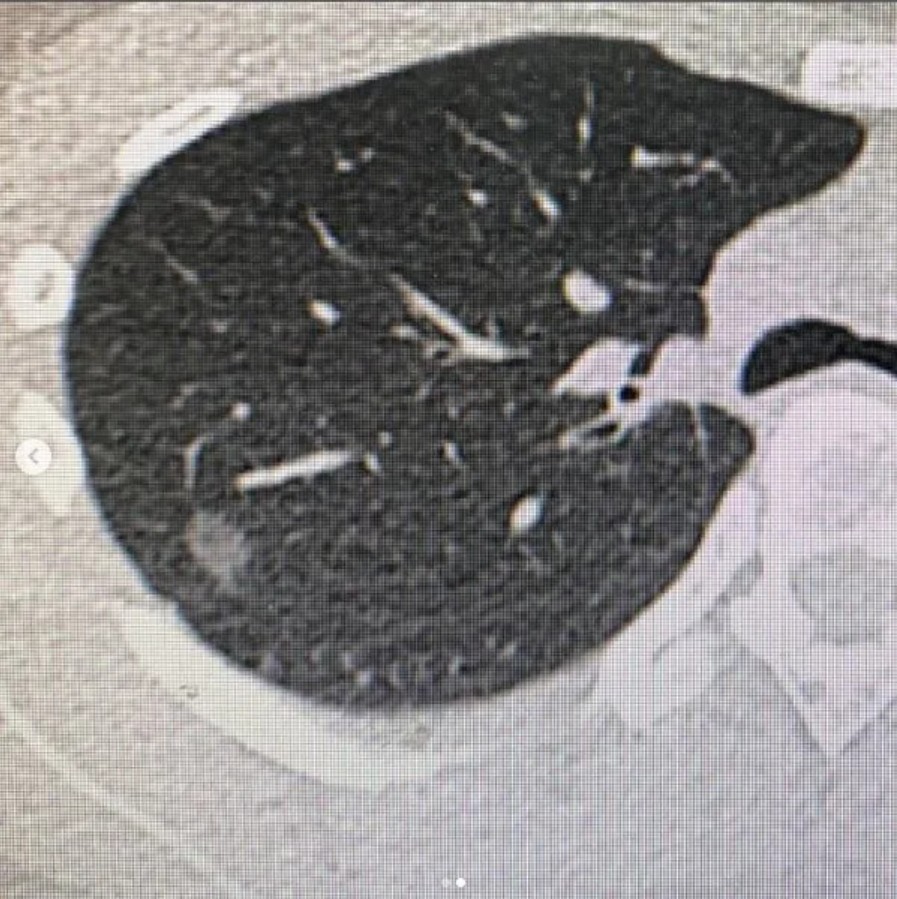

新冠後遺症:新冠病毒(COVID-19)作為一種全球性的流行病,已經對全球健康產生了巨大的影響。染上新冠病毒的患者,其病毒可能對免疫系統造成不良影響,導致免疫功能下降。一個弱化的免疫系統可能無法有效抵禦異常細胞的生長,這在某些情況下可能增加罹患肺癌的風險。

空氣汙染:科學研究已經證實,長期暴露於污染的空氣中會增加罹患肺癌的風險。空氣中的有害物質,如細顆粒物(PM2.5)、臭氧、二氧化硫和氮氧化物等,可以進入呼吸系統,對肺部組織造成損害。這些有害物質中的某些成分被認為是致癌物質,可能引發細胞變異和肺癌的發生。